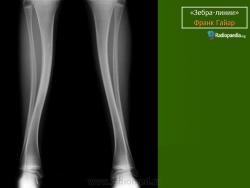

Рентгенологические изменения зависят от тяжести патологического процесса. Основным признаком является распространенный остеопороз всего скелета. Окружающие срастающийся перелом периостальные мозоли иногда достигают огромных размеров, симулируя опухоль (псевдосаркома). Отмечаются резкое истончение кортикального слоя, уменьшение диаметра кости. Характерна платиспондилия различной степени; позвонки приобретают двояковогнутую форму. Черепные швы расширены, с большим количеством непостоянных так называемых вормиевых косточек.

Рентгенологически. Выражен остеопороз костей, истончение кортикального слоя, следы множественных переломов и избыточного мозолеобразования, укорочение костей, сколиоз или кифосколиоз.